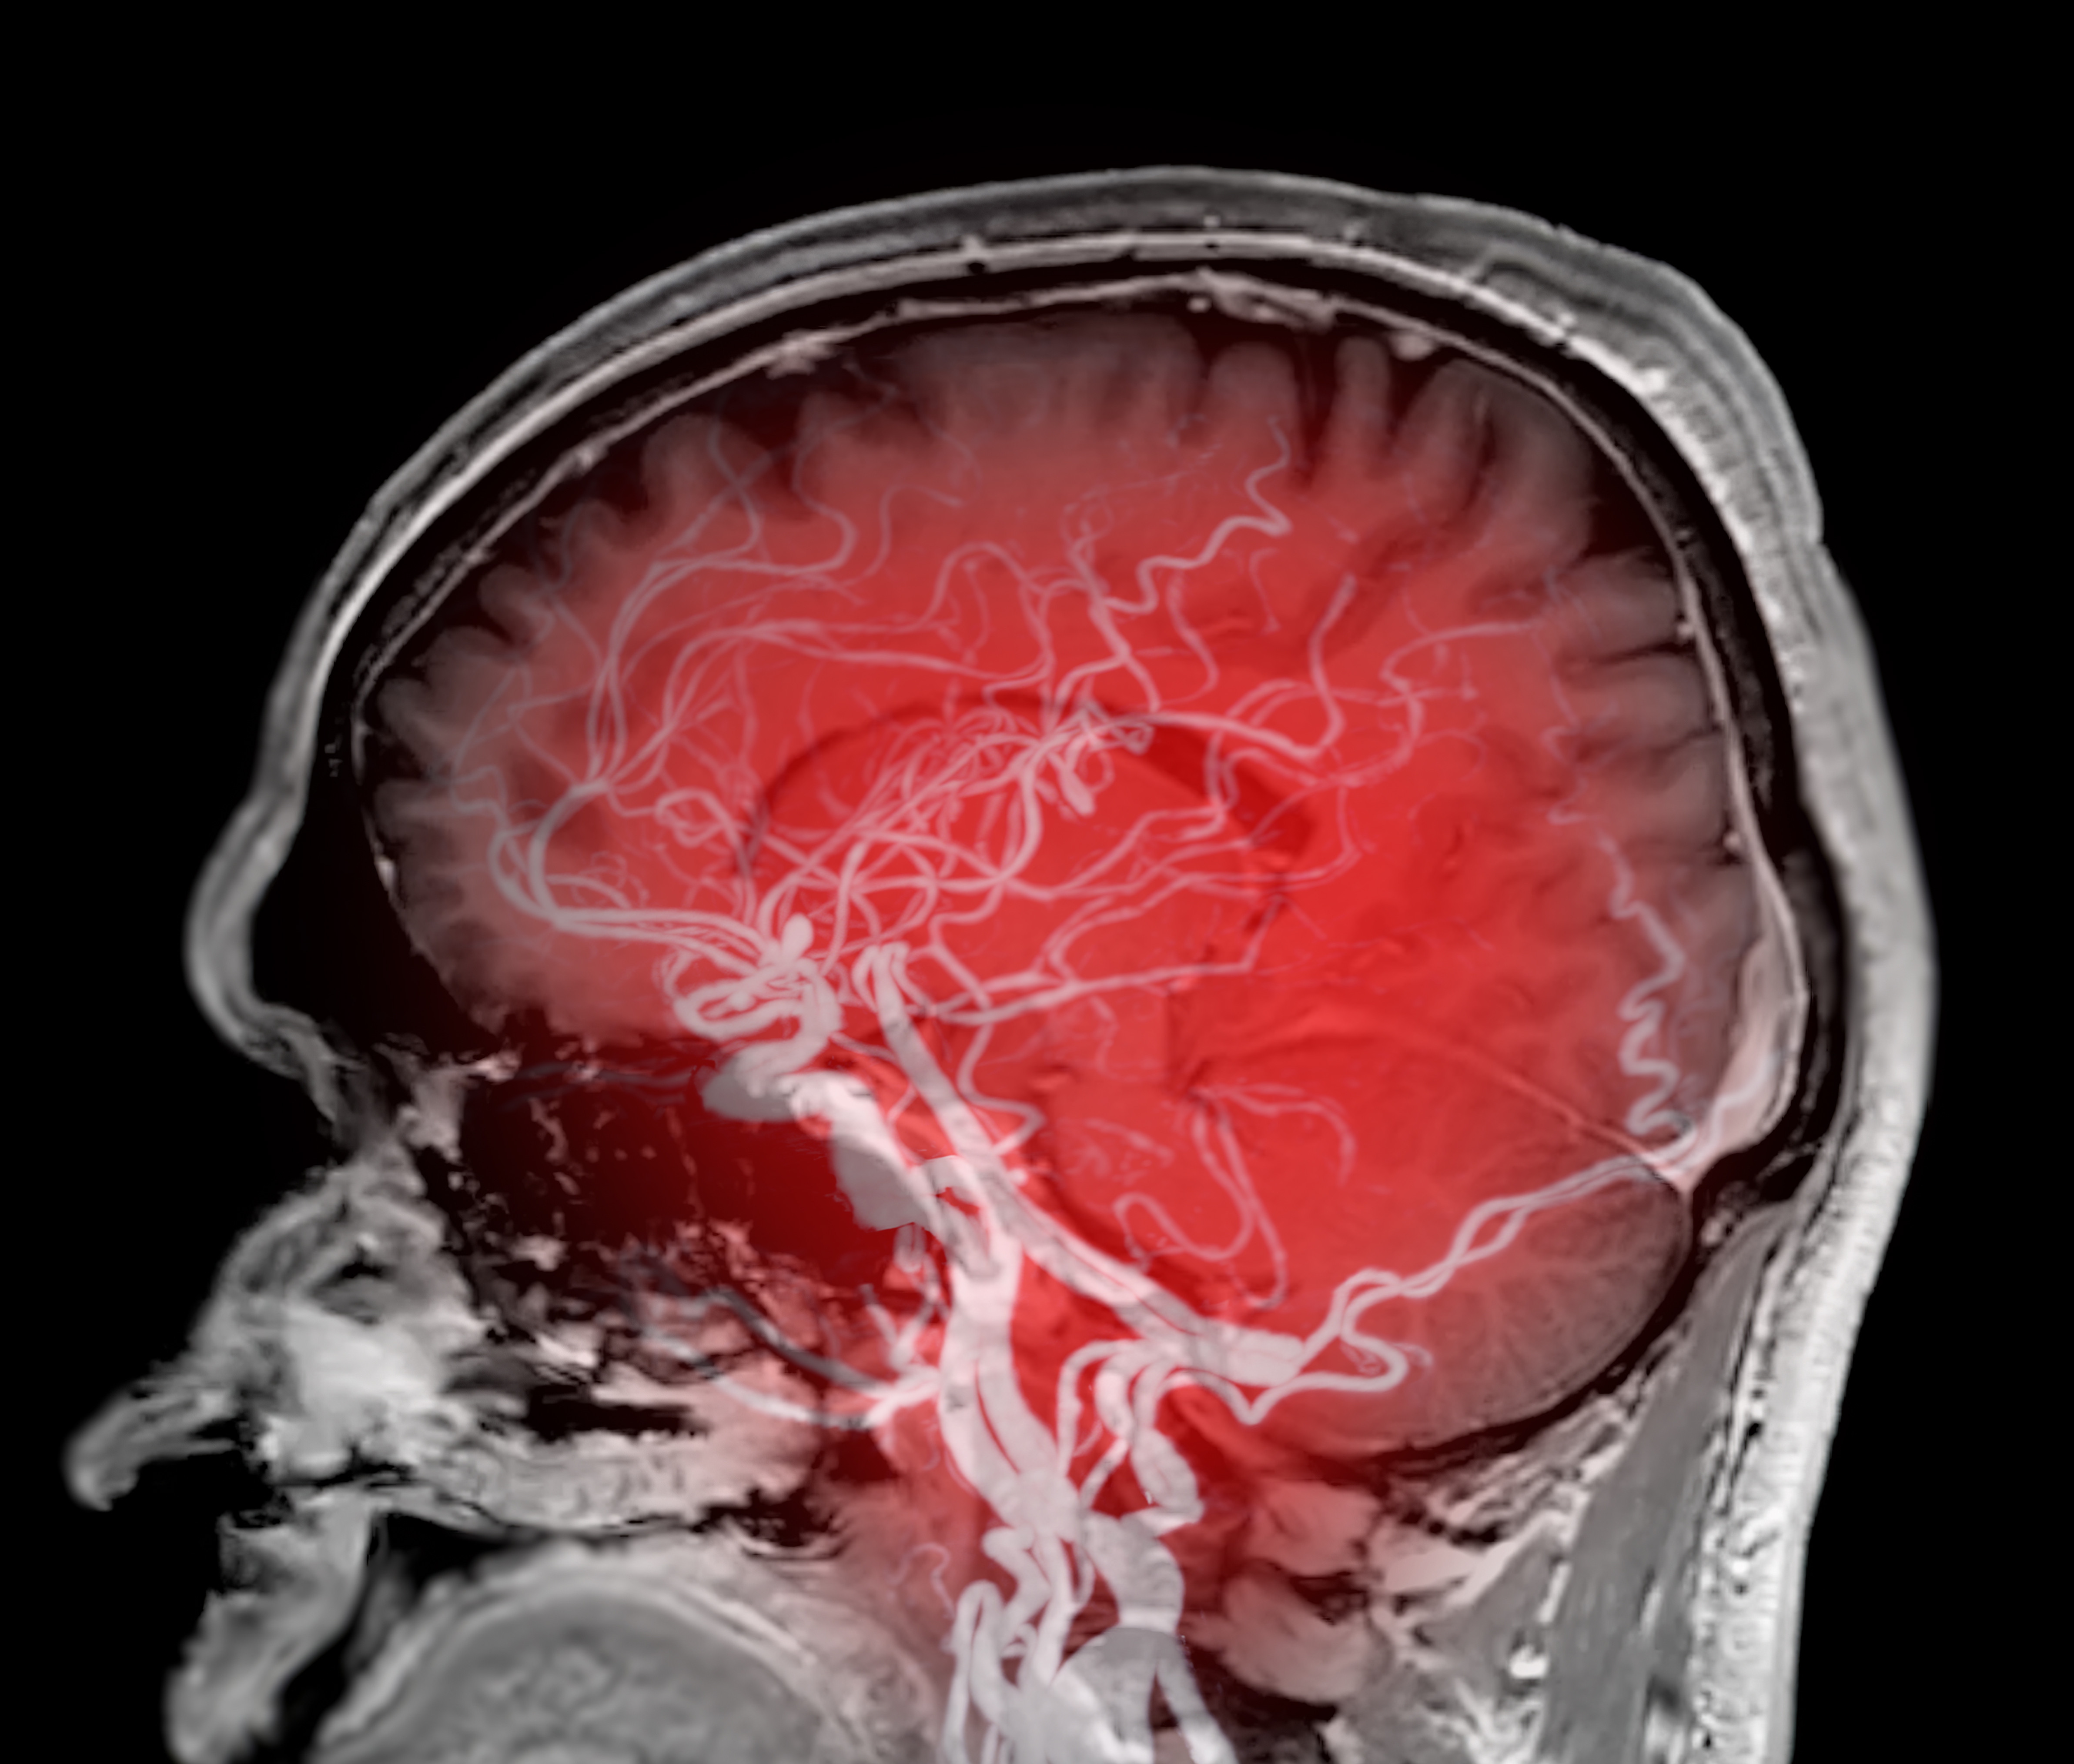

Nieleczone tętniaki mózgu zwiększają ryzyko chorób psychicznych